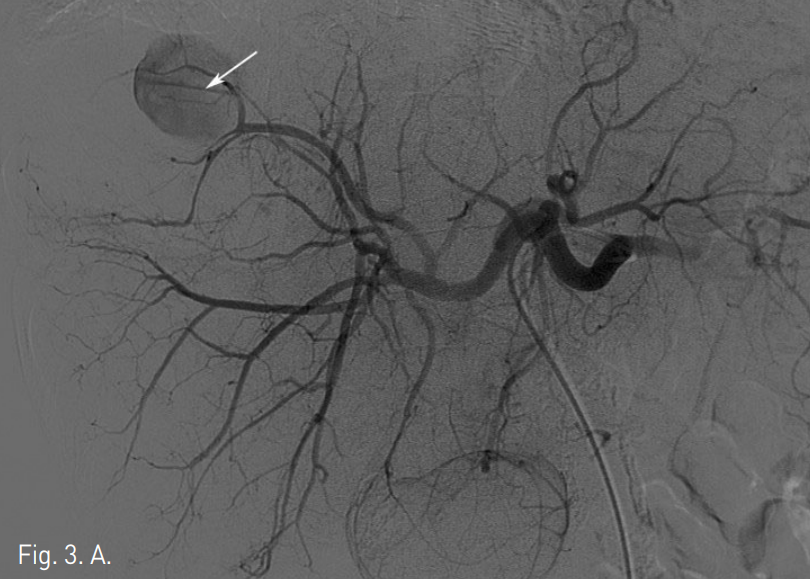

외래에서 시행한 복부 CT에서 간 우엽에 간동맥과 연결성을 보이는 2.5cm 크기의 가성 동맥류가 관찰되며 주위에 9cm 크기의 혈종이 있음. 간경변증을 보이고 있으나 간내에 간세포암종을 시사할만한 비정상적으로 조영증강되는 종괴의 소견은 관찰되지 않음(Fig. 1). 복부 MR에서 혈종의 뒤 안쪽으로 3.5cm 크기의 간세포암종으로 생각되는 병변이 관찰됨(Fig. 2).

Fig. 1

A, B. Axial (A) and coronal (B) CTimages of arterial phasereveal high density pseudoaneurysm and surrounded low density hematoma in the right lobe of the liver.